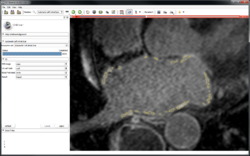

Slicer4 Quantitative Imaging tutorial

- The Slicer4 Quantitative Imaging tutorial guides through the use for Slicer for quantifying small volumetric changes in slow-growing tumors, and for calculating Standardized Uptake Value (SUV) from PET/CT data.

- Authors: Sonia Pujol, Ph.D., Katarzyna Macura, M.D., Ron Kikinis, M.D.

- Audience: Radiologists and users of Slicer who need a more comprehensive overview over Slicer4 quantitative imaging capabilities.

- Modules: Data, Volumes, Models, Change Tracker, PET Standard Uptake Value Computation

- Based on: 3D Slicer version 4.5

- The Quantitative Imaging dataset contains a series of MR and PET/CT data.